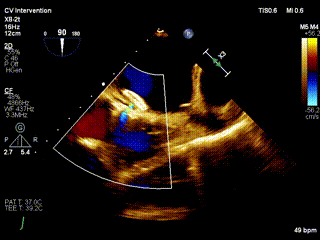

超声可见左向右分流束

患者于2021年11 月5 日在全麻下进行心房分流器植入。术中右心导管测量肺动脉19mmHg,PCWP 16mmHg,右房压4 mmHg,平均压力梯度5 mmHg。手术中全麻下使用经食道超声确认房间隔穿刺部位在卵圆窝附近,穿刺成功后在送入加硬导丝轨道支撑。根据患者病情及血流动力学结果,使用6 mm球囊预扩张,选择孔径6 mm心房分流器植入,透视下测量分流孔径6mm,孔径精准达标。植入后即刻效果明显,左房负荷超载和肺淤血明显减轻,血流动力学指标改善。肺动脉压降低至18mmHg,PCWP降至6mmHg,右房压降至3 mmHg,平均压力梯度维持在3 mmHg。心房分流器植入部位准确,形态良好,效果理想,释放卸载分流器。